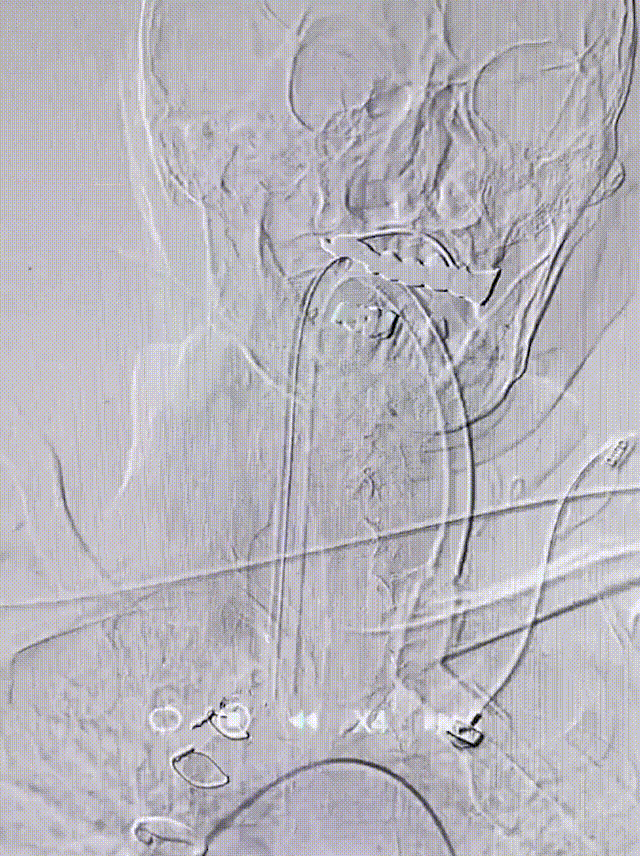

股动脉穿刺,置入8F动脉鞘。5F猪尾巴造影管行主动脉弓上造影,退出5F猪尾巴造影管后利用泥鳅导丝置入5F单弯造影管分别置于双侧颈总动脉行选择性造影显示:右侧大脑中动脉M1段闭塞,余脑血管未见明显异常。

8F导引导管置于右侧颈总动脉未端,在路图引导下利用0.035in泥鳅导丝置入6F 中天天巡®Pro血栓抽吸导管置于右侧颈内动脉C2段,退出泥鳅导丝,置入0.014in微导丝和Rebar18微导管在路图指引下顺利通过右侧大脑中动脉闭塞部位,远端置于M2段中部,退出微导丝,行微导管造影显示:M1段中远端血流缓慢。

沿微导管将6F 中天天巡®Pro血栓抽吸导管置于右侧大脑中动脉起始部血管闭塞部位,接负压抽吸,可以血栓吸出,血流恢复通畅,血管一把开通。

术后造影

复查造影示右侧大脑中动脉再通,而TICI分级3级,手术成功。